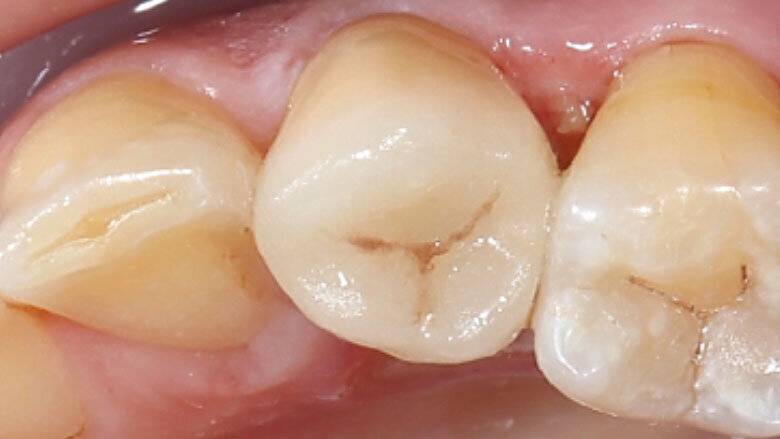

Fig. 12. Desde vestibular no se observaban transiciones entre la restauración y el diente.

Fig. 14. Resultado: integración altamente estética de la restauración durante la revisión al cabo de seis meses.

Acondicionamiento y colocación

Se grabó la cerámica de feldespato con ácido fluorhídrico para crear un patrón de grabado microrretentivo y a continuación se silanizó. Se acondicionó la cavidad con ácido fosfórico y un adhesivo. Para la fijación adhesiva se calentó el composite Micerium (Micerium, Avegno, Italia) en el color UD2, a fin de fluidificarlo para la inserción. Tras la fotopolimerización y la eliminación de los restos de composite, la restauración se integró perfectamente en la sustancia dental natural gracias a sus excelentes propiedades fotoópticas.